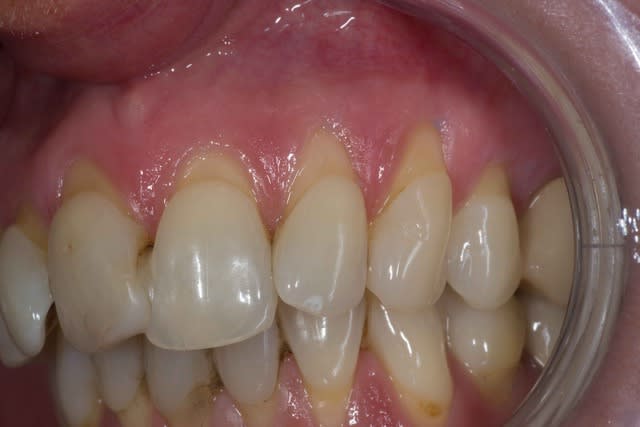

Img 2078 jexjqo - Eugenol

Img 2079 zq4nhx - Eugenol

Img 2076 afcxn3 - Eugenol

tillcky luke : l'homme qui dégaine son scalpel plus vite que son ombre.

Effectivement David tu ne pouvais pas mettre en application de façon plus rapide.

Merci de poster ce cas et ta chirurgie même si tu sais ce que je pense de la technique de tunnélisation ;-))

Oui effectivement et la j'ai trouvé la limite de cette technique j'ai pas bien réussi a tracter mon lambeau :/.

Je pense qu'a partir de maintenant je vais me mettre au LDC histoire de me faire vraiment la main avec cette technique.